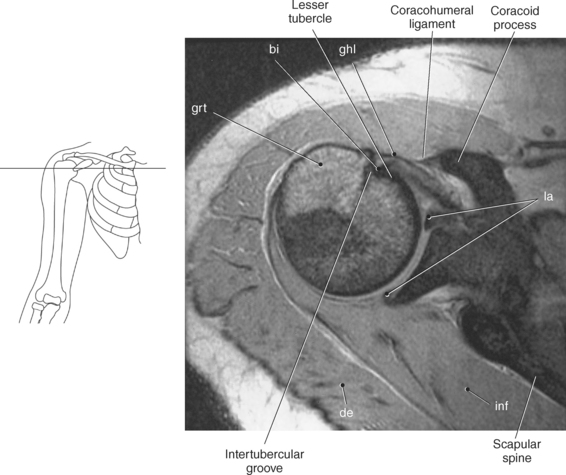

The edge of the glenoid fossa is surrounded by a fibrocartilaginous ring termed the glenoid labrum (glenoid lip) (Figure 9.17). The glenoid labrum is a fold of the articular capsule, which functions to deepen the articular surface of the glenoid fossa. Superiorly, the labrum blends with the long head of the biceps brachii muscle. In cross section it appears triangular (Figure 9.18). The three glenohumeral ligaments (superior middle, and inferior) are thickenings of the fibrous capsule that surrounds the shoulder joint; they contributes to the formation of the glenoid labrum (Figures 9.17 and 9.19). They extend from the supraglenoid tubercle of the scapula to the lesser tubercle of the humerus. Also aiding in strengthening the fibrous capsule is the coracohumeral ligament that passes from the lateral side of the coracoid process of the scapula to the anatomic neck of the humerus (Figure 9.19). The coracoacromial ligament is another important ligament located on the anterior portion of the shoulder. As this ligament joins the coracoid process and acromion, it forms a strong bridge, termed the coracoacromial arch, which protects the humeral head and rotator cuff tendons from direct trauma and prevents displacement of the humeral head superiorly (Figures 9.17 and 9.19). The coracoclavicular ligaments help to maintain the position of the clavicle, in relation to the acromion, by spanning the distance between the clavicle and coracoid process of the scapula (Figure 9.19). The acromioclavicular ligament, at the acromioclavicular joint, provides support for the superior surface of the shoulder (Figures 9.17 and 9.19). The transverse humeral ligament is a broad band of connective tissue passing from the greater tubercle to the lesser tubercle of the humerus, forming a bridge over the intertubercular groove for protection of the long head of the biceps tendon (Figure 9.19). The ligaments of the shoulder are demonstrated in Figures 9.20 through 9.30.

The humerus is a long bone that articulates with the scapula superiorly and the radius and ulna inferiorly. It consists of a body or shaft, a lower end (distal end), and an upper (proximal) end (Figure 9.13). The proximal end is formed by the head of the humerus. Two tubercles project from the humeral head to provide attachment sites for tendons and ligaments. The lesser tubercle is located on the anterior surface of the humeral head, whereas the greater tubercle is located on the lateral surface of the humeral head (Figures 9.12 through 9.15). The tubercles are separated by the intertubercular (bicipital) groove, which is bounded by the crests of the lesser and greater tubercles as it descends the humerus (Figures 9.9 and 9.13 through 9.15). The humerus has two necks, the more proximal anatomic neck and the surgical neck, located inferior to the tubercles just distal to the humeral head (Figures 9.13 and 9.16). In the middle of the body or shaft of the humerus, on the anterior surface, is the roughened area of the deltoid tuberosity that gives attachment for the deltoid muscle (Figure 9.13).